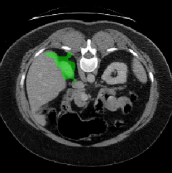

Figure 3 illustrates the specific segmentation results on the SABS dataset under Setting 1. Our model demonstrates higher accuracy in segmentation and effectively reduces unnecessary segmentation. Even under Setting 2, where the test class is entirely invisible to the model, our model performs well, as depicted in Figure 4. Given that SABS is a multi-organ dataset with many organs of small size, precise segmentation proves challenging. However, our model excels, particularly in the scenario of completely invisible classes, which closely resembles real-world conditions. Figure 4 highlights our model’s ability to accurately segment very small target organs, such as the right kidney. In contrast, the ADNet method fails to produce effective segmentation predictions, and other methods exhibit varying degrees of over-segmentation. On the CMR dataset, as shown in Table 2, our model generally outperforms others.

The predictions produced by the different prototypes are shown in Figure 6. Among them, in the segmentation of liver organs, it can be seen that the use of a single support prototype cannot produce a comprehensive segmentation, and the use of multiple support prototypes has significantly improved the effect, and the combination of multiple support prototypes and query prototypes can produce a more comprehensive segmentation. On the left kidney, the use of a single supporting prototype will produce a relatively large amount of over-segmentation, which will be reduced after the introduction of the query prototype, but some pixels are still over-segmented. However, the combination of multiple support prototypes and query prototypes can avoid over-segmentation.